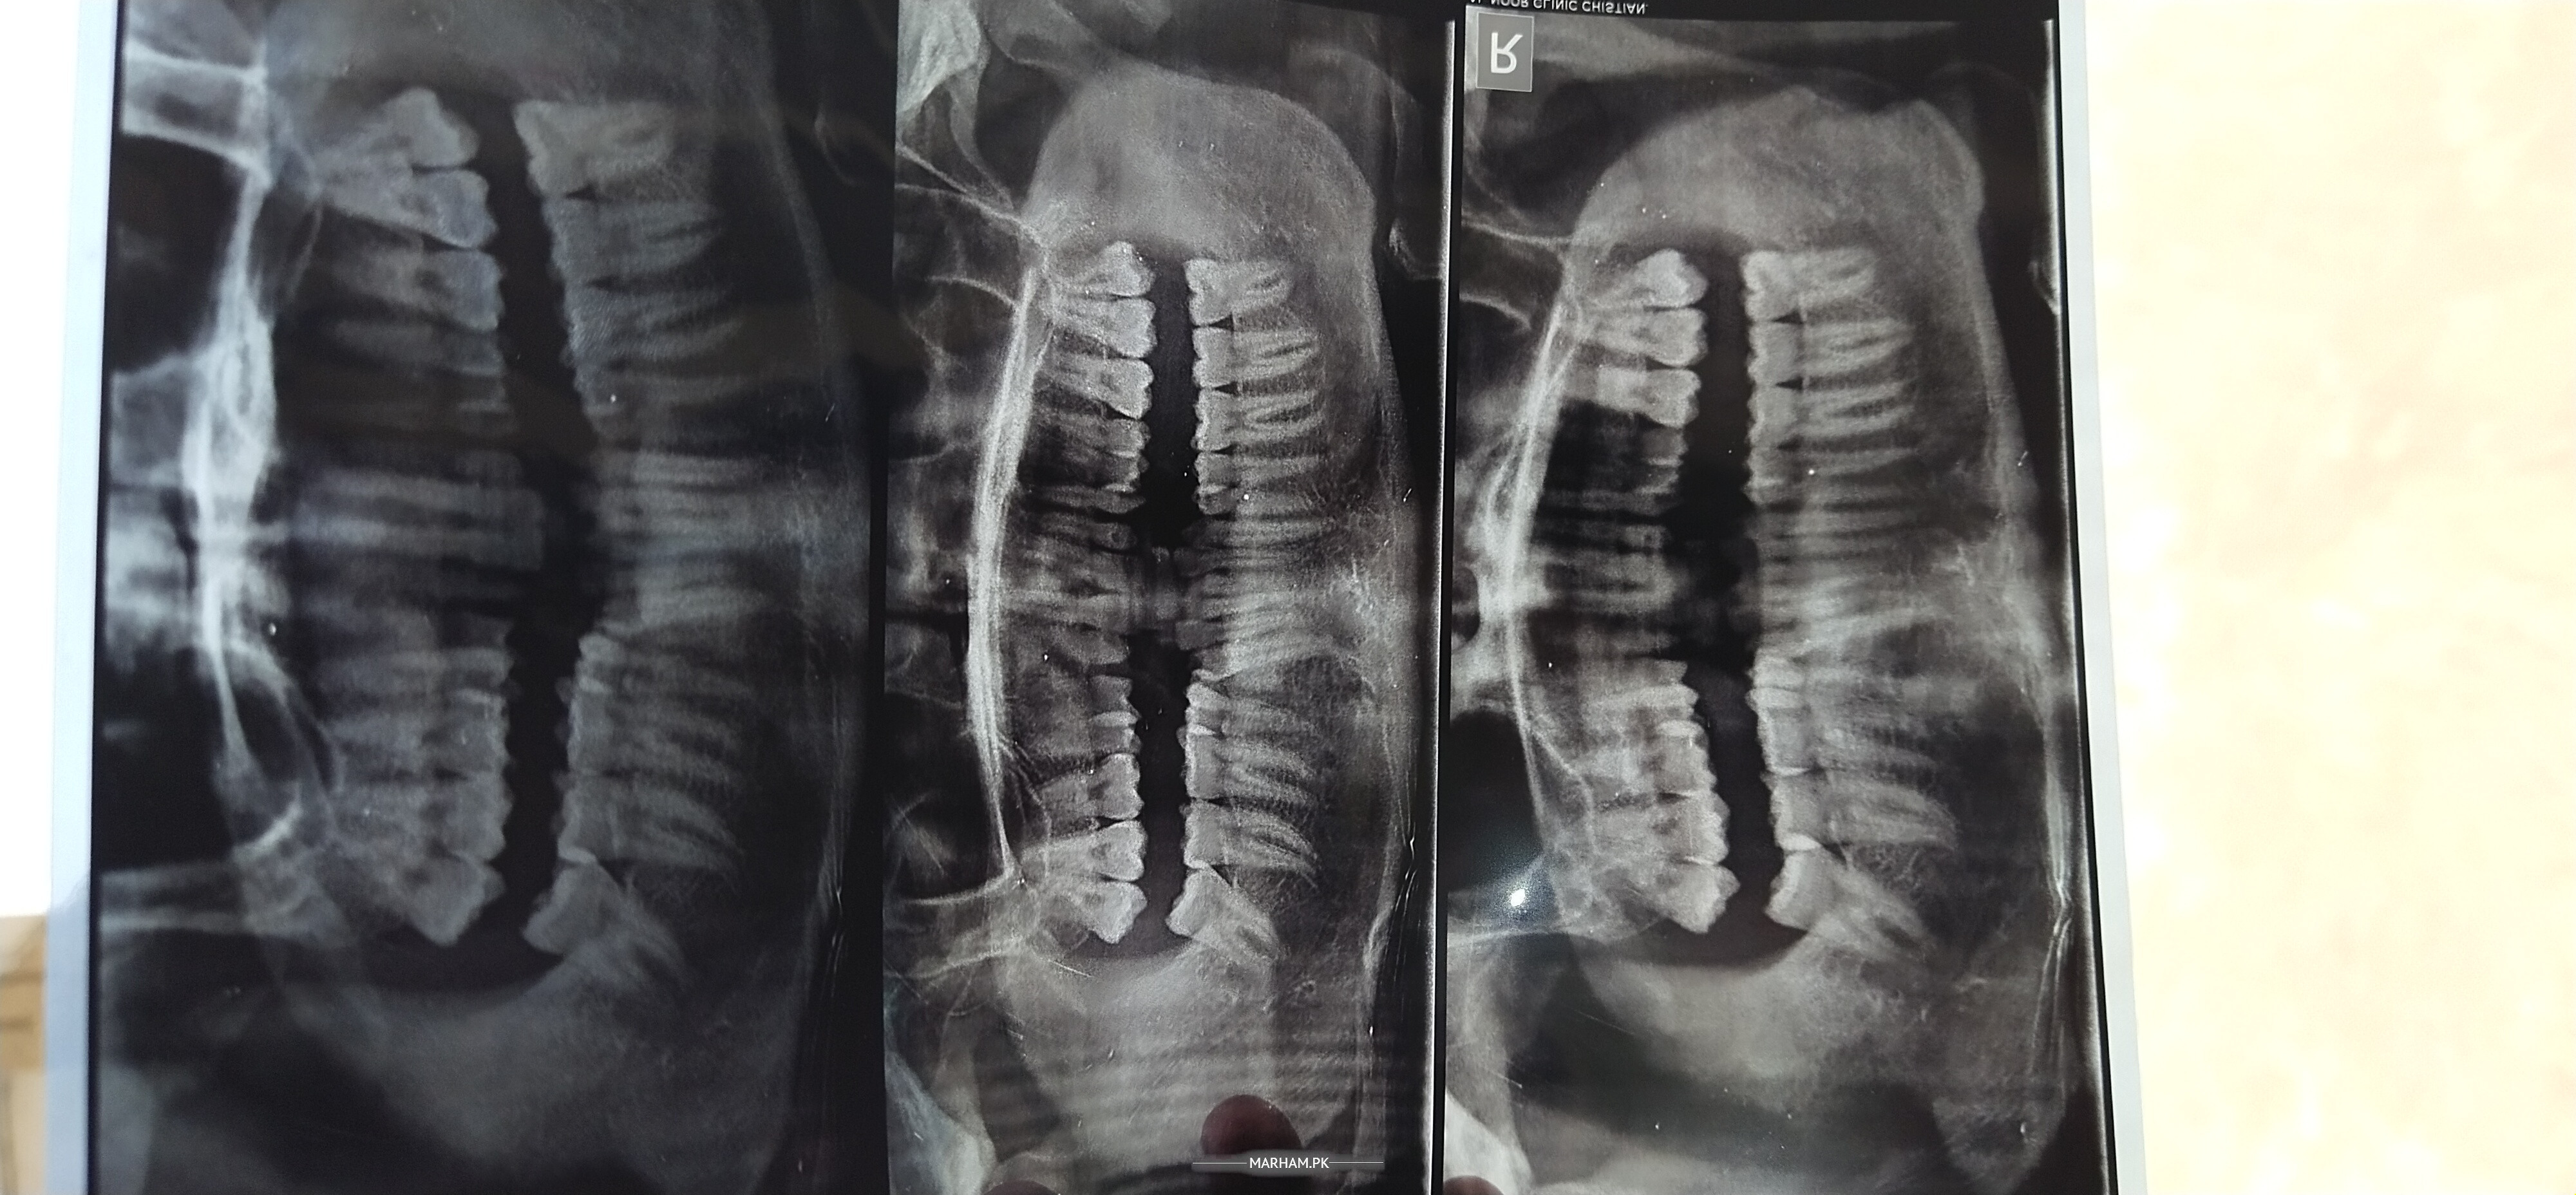

Asking For Self, Male 20, chishtian

one of my upper canion teeth is missed teeth shed hony bad aya h asa procedure ky 1 wohi teeth plant not caping jesy ky 2 side waly teeth b root canal hone gay r 3 teeth py teeth aisy h natural rahain bs sirf new teeth implant ho

g ek opg xray chaiyee hoga maybe canine impacted hoo apka otherwise implant krva skty hn aap